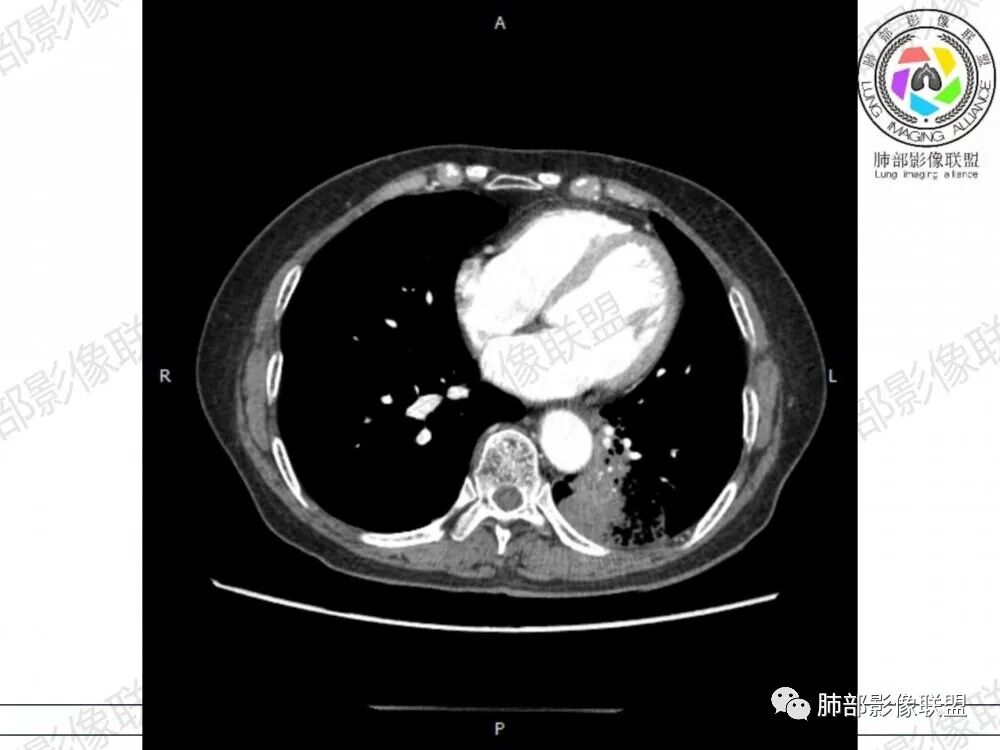

胸CT:左下叶胸膜下大片斑片影,长轴沿胸膜分布,实变、GGO混杂,磨玻璃边界清晰,粘液密度,小叶内间隔增厚,支气管进入后堵塞(枯枝),增强轻中度强化,血管造影征。常规考虑:肺腺癌?淋巴瘤?鉴别不典型病原体感染。

2、影像表现:无肺气肿背景,病变定位于左肺下叶背内侧基底段,病灶呈不规则团块影,靠近胸膜侧,其内密度不均匀,内见空洞、实变及磨玻璃影,磨玻璃影呈碎石路征,边界清楚,实性肿块边界膨隆,其内见空洞。空洞周围比较实。病灶较大的支气管通畅,细小的支气管成“枯枝征”。无胸膜增厚及胸膜腔积液,增强扫描呈中度强化,见血管造影征。

1、粘液型腺癌仅占肺原发腺癌的3%左右,粘液多,易气道播散,支气管破坏不明显,不仅是大的支气管,小的支气管大多也没破坏,较大的支气管通畅,细小的支气管充满粘液,从而形成“枯枝征”,本病例病灶内可见枯枝征,是诊断粘液腺癌特点之一。

2、典型的粘液腺癌,收缩力很弱,肺泡壁断裂常有,张力存在,早期较少出现张力表现,破坏力偏弱,支气管与肺血管大多保留,所以增强病灶内见强化血管影(血池),也是粘液腺癌另一个特点。